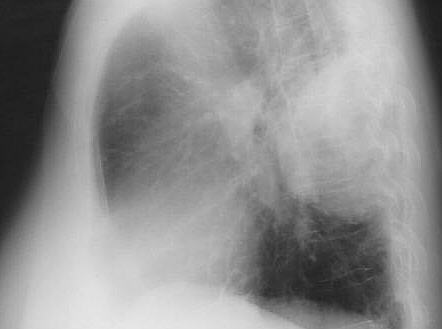

AP viewleft lateral view

Chest X-Ray demonstrating 10.0x6.0 cm mass in Left lower lobe, apical segment.